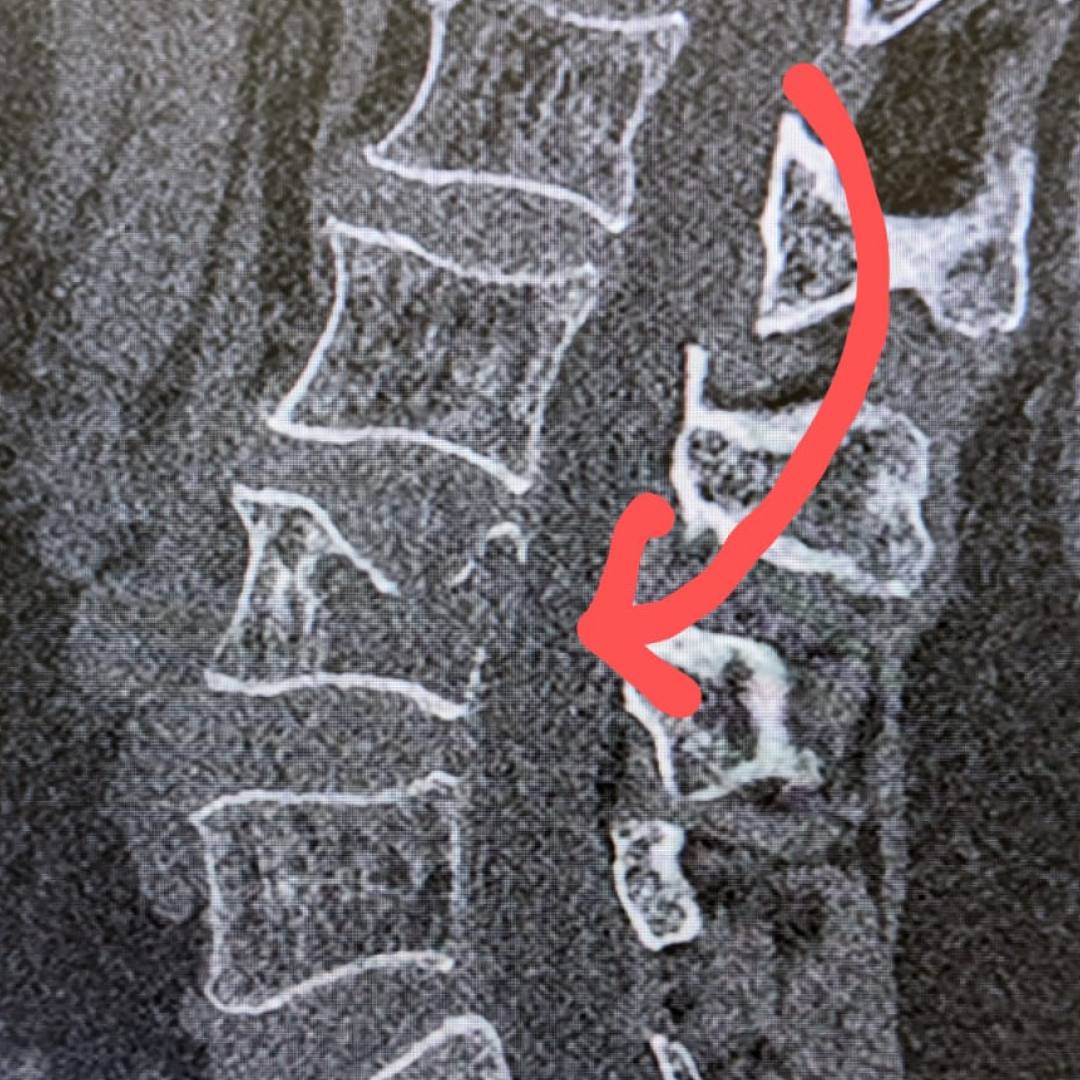

При магнитно-резонансной томографии был выявлен перелом четвертого поясничного позвонка на фоне мягкотканого образования в теле позвонка, вследствие чего пациентке было предложено выполнить дообследование в виде компьютерной томографии.

По результатам КТ и МРТ было заподозрено наличие агрессивной гемангиомы или плазмоцитомы позвонка как причины перелома.